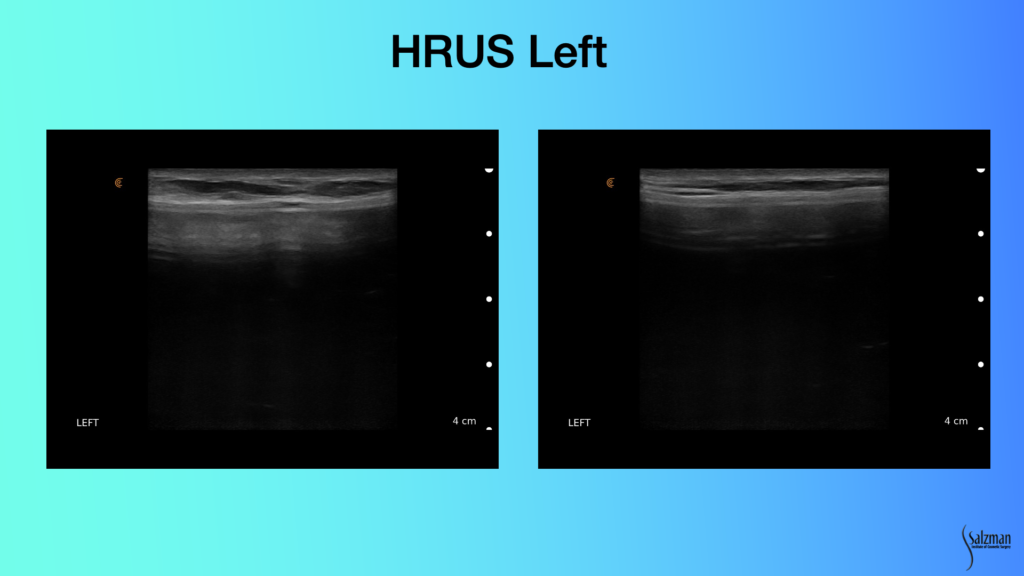

Patient Causes Post-Operative Complication

The only time I ever use drains for breast surgery is when I put in Strattice or I do a capsulectomy. So, in this case, I put a drain in. On day four the patient decided to remove her own drain. When she came to the office two days later, I was concerned she may have caused a seroma. With ultrasound, I was able to see a little tiny bit of fluid, which I decided to watch. I examined her again with ultrasound about a week later, and the fluid had been reabsorbed.

If I didn’t have ultrasound, I would have sent her to a radiologist for another $1,500 exam and aspiration. He would say he’s afraid to put a needle in because it’s an implant. With ultrasound, I know that I can stick the seroma and not stick the implant. I can see it. It’s so easy.

In summary, high-resolution ultrasound allowed for an immediate, day of, consult diagnosis of both the seroma and broken implant. It led to a treatment plan that day. I scheduled an appropriate procedure and afterwards was able to use ultrasound to assess that when the patient decided to remove the drain, it was probably okay.